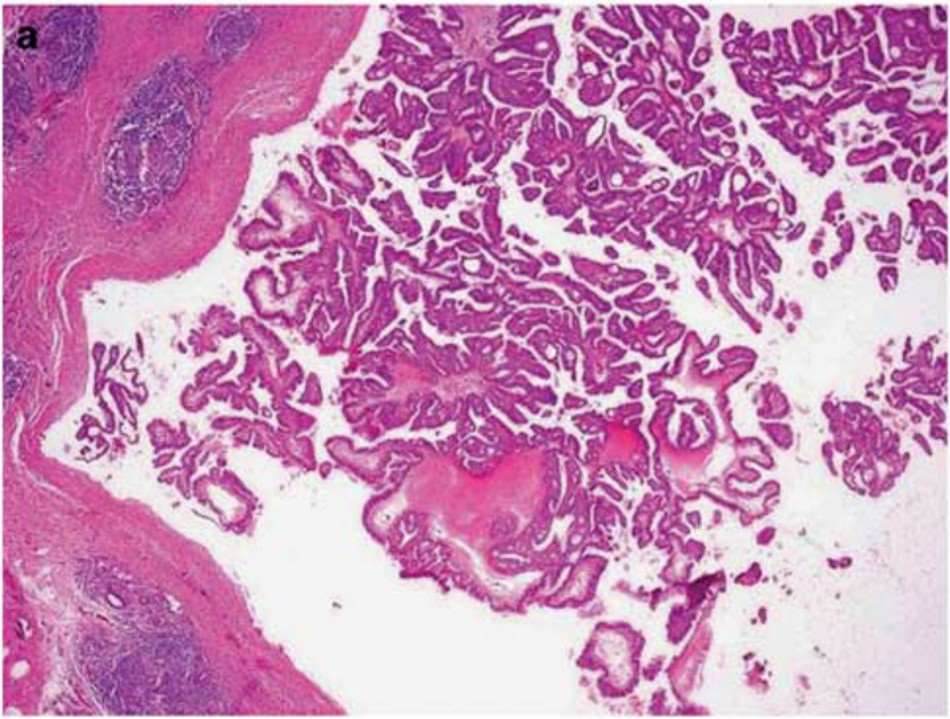

Papillary breast carcinoma (PBC) is a rare and complex subtype of breast cancer that presents unique challenges in both diagnosis and treatment. Unlike more common breast cancer subtypes, PBC is characterized by a distinctive papillary growth pattern, where tumor cells proliferate along delicate fibrovascular cores, forming finger-like projections. This architectural feature, along with the often well-differentiated and low-grade nature of PBC, can make it easily mistaken for a benign lesion, leading to delayed diagnosis and suboptimal management.

Fig.1 Examples of papillary carcinoma of the breast displaying papillary architecture features. (Hameed O., et al. 2009)